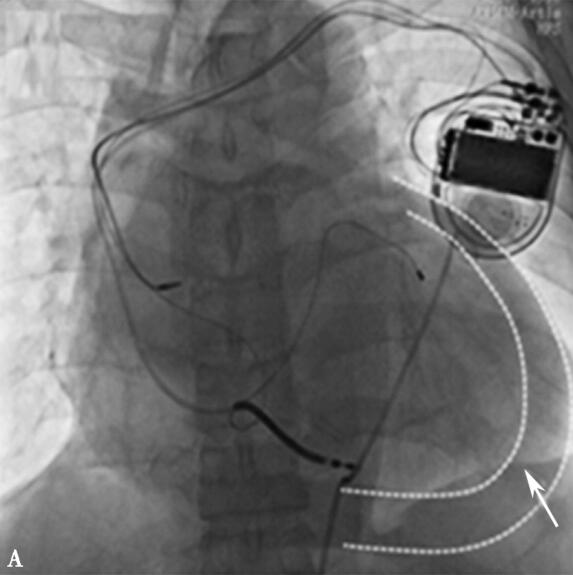

入院心电图:窦性心律,完全性左束支传导阻滞,QRS波时限200ms。心脏超声:左室射血分数:0.32,左心室内径:77mm,室壁运动幅度普遍减低。诊断:①扩张性心肌病:心功能Ⅲ级;②完全性左束支传导阻滞。根据器械植入指南,该患者为行CRT或CRT-D植入术的Ⅰ类适应证。在充分药物治疗基础上,心功能恢复至Ⅱ级水平,行CRT-D植入术(4193左室电极至心侧静脉远端),术中测试起搏电极参数良好,手术过程顺利,术后心电图:心房感知双心室起搏心电图。术后第二天患者下地活动自觉无不适,但患者心率偏快90次/分左右,心电图:间断左室不起搏,程控起搏电极参数左室阈值升高为3.0V(0.5ms),右室除颤电极及右房电极参数良好,给予提升左室输出电压后可见双心室完全起搏。同时给予控制心率、强心等相关药物治疗。术后第3日,患者出现心悸、胸闷、气短,伴膈肌跳动感,大汗。查体:端坐呼吸,口唇发绀,周身湿冷,血压85/60mmHg,双肺呼吸音粗,可闻及湿啰音,心率110次/分,律齐,心音遥远,可见膈肌跳动。心电图证实左室不起博,起搏器参数测试发现:最大电压7.5V(1.5ms)无法夺获左室,右室除颤电极及心房电极参数良好。患者心率快、血压低,心源性休克状态,考虑心包压塞可能性大,紧急推送导管室心脏透视,见中等量至大量心包积液(图3-5-2A),紧急行剑突下心包穿刺,应用猪尾导管心包腔引流,抽出200ml不凝血时患者症状较前缓解,共抽出不凝血约600ml,此时测血压:119/70mmHg,心率:80次/分,透视下见心包积液微量,连接心包负压吸引器后安返病房(图3-5-2B),此时查心脏超声:左室后壁后方心包腔内见6mm液性暗区。心包引流管通畅,患者无胸闷、心悸及胸痛不适,严密监测患者生命体征,6小时后复查心脏超声未见心包积液;同时继续抗心力衰竭、预防感染药物治疗。36小时后患者无不适主诉,生命体征平稳(停用升压药物),仍为房颤心律,连续两次复查心脏超声未见心包积液,24小时心包引流量5ml,给予拔出心包引流管。继续抗心力衰竭药物治疗,1周后患者一般状态较好,夜间气短、憋醒症状明显好转,病区内活动无胸闷、气短症状发作。患者因担心再次手术风险,拒绝进一步行调整左室电极导线手术。予以保留起搏器除颤功能,关闭了起搏功能后,病情好转出院。

图3-5-2 左前斜45°见心包积液影像 A:两虚线间为心包积液显影,如箭头所示